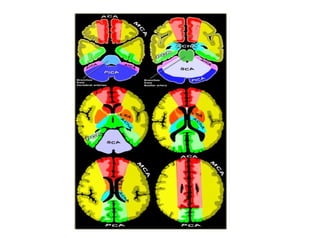

b) Cerebral Arterial Territory :

1-Posterior Inferior Cerebellar Artery

2-Superior Cerebellar Artery

3-Branches from vertebral and basilar artery

4-Anterior Choroidal artery

5-Lenticulostriate arteries

6-Anterior cerebral artery

7-Middle cerebral artery

8-Posterior cerebral artery

1-Posterior Inferior Cerebellar Artery (PICA in blue)

-The PICA territory is on the inferior occipital

surface of the cerebellum and is in equilibrium

with the territory of the AICA in purple which

is on the lateral side

-The larger the PICA territory , the smaller the

AICA and vice versa

2-Superior Cerebellar Artery (SCA in grey)

-The SCA territory is in the superior and tentorial

surface of the cerebellum

-These branches supply the medulla oblongata

(in blue) and the pons (in green)